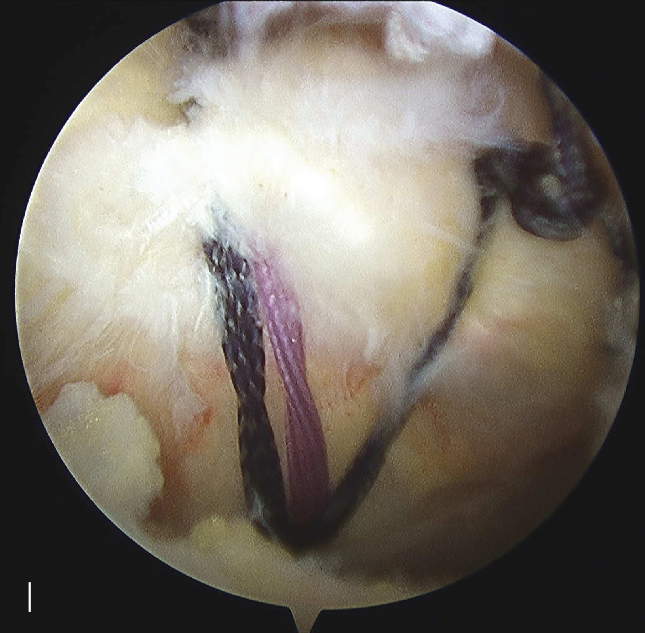

肩袖部分撕裂的修复

前方关节囊微紧缩

后下方关节囊切开术